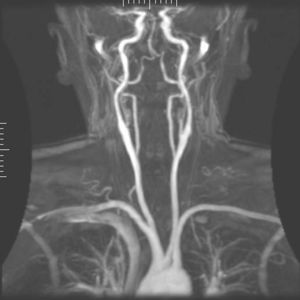

Maximum intensity projection of an MRA covering from the top of the heart to just below the circle of Willis

Occasionally, MRA directly produces (thick) slices that contain the entire vessel of interest. More commonly, however, the acquisition results in a stack of slices representing a 3D volume in the body. To display this 3D dataset on a 2D device such as a computer monitor, some rendering method has to be used. The most common method is Maximum intensity projection (MIP), where the computer simulates rays through the volume and selects the highest value for display on the screen. The resulting images resemble conventional catheter angiography images. If several such projections are combined into a cine loop or QuickTime VR object, the depth impression is improved, and the observer can get a good perception of 3D structure. An alternative to MIP is direct volume rendering where the MR signal is translated to properties like brightness, opacity and color and then used in an optical model.